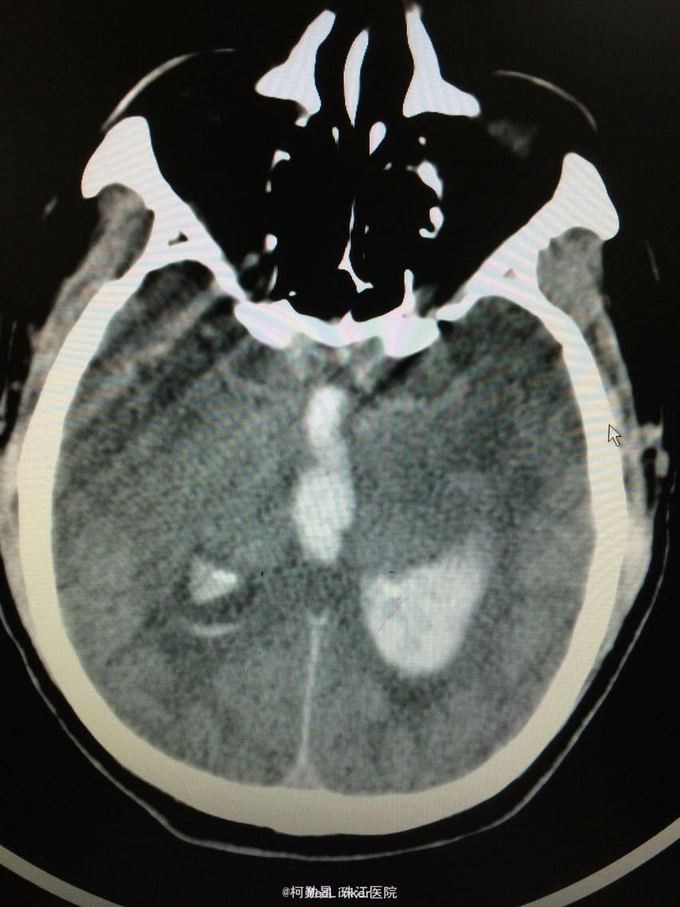

主诉:突发意识障碍4小时 病史:患者57岁男性,入院前一天晚上突发意识不清,伴呕吐胃内容物多次,无肢体抽搐等,随即由家人呼叫120送至我院,急诊行头颅CT提示左侧基底节区出血破入脑室。既往高血压病史10多年

查体:神志不清,双侧瞳孔散大,对光反射消失,四肢肌张力正常,肌力无法检查 辅助检查:头颅CT提示左侧基底节区出血破入脑室

诊断:左侧基底节区出血并破入脑室 处理:急诊行侧脑室钻孔外引流术,术后并予积极抢救,最终抢救无效死亡

随访:患者最终死亡。 讨论:该患者属于典型的高血压性脑出血,且出血量多,预后不良。壳核和丘脑是高血压性脑出血的两个最常见部位。典型可见三偏体征(病灶对侧偏瘫、偏身感觉缺失和偏盲等),大量出血可出现意识障碍,也可穿破脑组织进入脑室,出现血性CSF,直接穿破皮质者不常见。